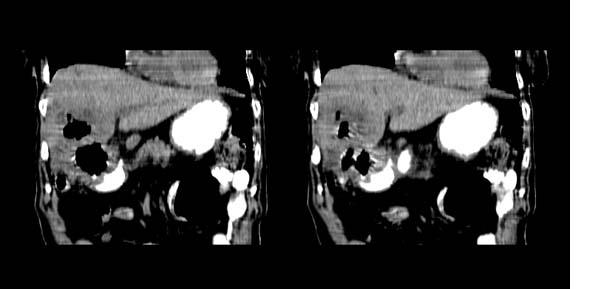

以下是引用bailaode在2008-6-12 22:10:00的发言:[br]资料中未提及患者有无急腹症体征,这个很重要。[br] ct表现:肝内境界模糊之低密度灶,内有含对比剂之液气平面.(提示肝内病灶与胃肠道沟通) [br] 1、根据“长城干红 ”所提供的资料“患者,女,74岁,黑便月余,消瘦,一般状况差,白细胞1万四千”,是否可认为是个慢性病程?那么我首先考虑:十二指肠结核,十二指肠--胆管瘘,继发胆道逆行感染肝脓肿形成。[br] 2、如有急腹症体征则考虑:十二指肠溃疡穿孔?十二指肠占位伴穿孔?

以下是引用拾荒者在2008-6-13 22:13:00的发言:[br]病灶与升结肠、肝脏及十二指肠关系密切,且结肠降段见造影剂影,支持结肠与十二指肠瘘形成,原因及原发病在哪不好定,不过,虽说有风险,但还是应该手术治疗,单纯抗感染估计不行。